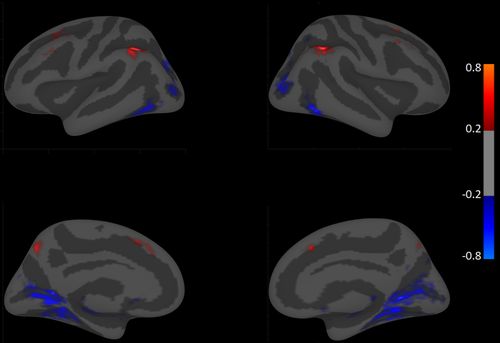

Results: The BAT’s interface is shown in figure 1. The workflow is as follows: First the user imports a list of subjects and a measure of interest using the “Import PGUIDS & Independent Variable” button (fig. 1-1). Users then select an fMRI contrast and covariates using the available options (fig. 1-2). Afterwards the user generates a design matrix and can preview it by clicking the “Create Design Matrix” button (fig. 1-3 & 1-4). Optionally, the user can save a local copy of the design matrix as a text file (fig. 1-5). The last step involves setting the parameters for the type of analysis the user would like to perform (fig. 1-6). An example output for an analysis comparing the 2-back vs. fixation contrast of the N-Back on the cortical level between males and females is shown in figure 2. Here, Cohen’s d maps are thresholded at ≥ 0.2 where red areas represent bigger BOLD activation in males and blue areas represent bigger BOLD activation in females.